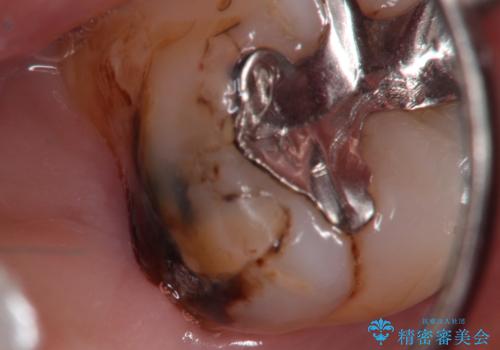

- 定期検診にて虫歯を見つけ、メタルボンドクラウンにて修復補綴治療を行なっております。

歯肉縁下まで虫歯が進行していたため歯周外科を併用して治療を行なっております。